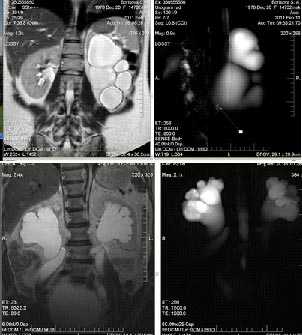

Кисты почек

В обеих почках не расширены чашечки, но визуализируются кисты, что и было доказано на МР-урографии.

МР-урография показывает преимущественно кистозное поражение (стрелка) в верхнем полюсе левой почки с отеком.

Конкременты в правой почке. МР-урография подтверждает присутствие дефекта (стрелка) в почечной лоханке.

Обследование женщины с послеродовой гематурией.